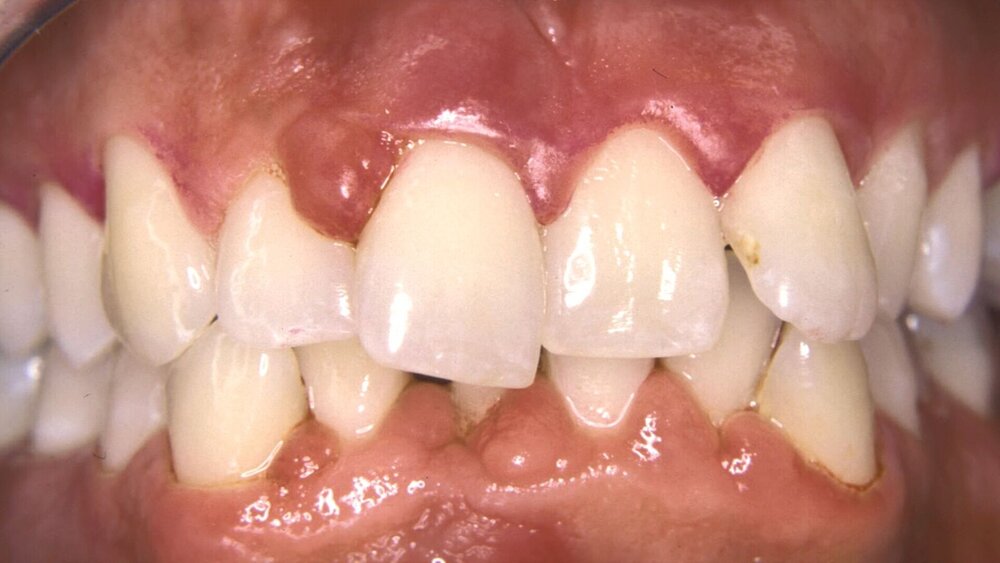

Der Falltyp 2 der Stadium-IV-Parodontitis beschreibt den Patienten mit pathologischen Zahnwanderungen, gekennzeichnet durch Zahnelongationen, -lückenbildungen und -auffächerungen, die für eine kieferorthopädische Korrektur geeignet sind. Die betroffenen Zähne weisen zumeist stark fortgeschrittene Attachmentverluste und Entzündungszeichen auf (Abbildung 1).

Die pathologische Zahnwanderung [Brunsvold, 2005] ist eine häufige Folge des parodontalen Attachmentverlusts bei Parodontitis-Patienten im Stadium IV, die sich in Form von Zahnstellungsveränderungen, -auffächerungen (Flaring) und -elongationen äußert. Deren Korrektur erfordert OT nach Abschluss der Parodontaltherapie. Die kieferorthopädische Behandlung dieser Folgeerscheinungen beinhaltet in der Regel intrusive, retrusive und angleichende Zahnbewegungen, die potenziell negative Auswirkungen (weiterer parodontaler Attachment- oder Knochenverlust, verstärkte Gingivitis oder verstärkte Wurzelresorption) oder sekundäre Effekte (unerwünschte ästhetische Ergebnisse wie Gingivarezession und Verlust der Interdentalpapille) auf die betroffenen Zähne haben können.